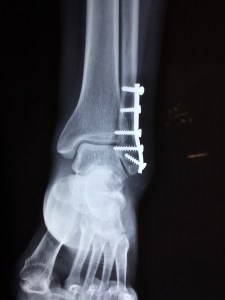

The advice here in an ideal situation is to take painkillers, ideally with an anti-inflammatory and rest, keeping the ankle elevated. If it’s clear it’s broken or something just isn’t right, there’s no chance you’re walking on it, keep the pressure off. You’re going to have to get some help, if it’s not going to come, you’re going to have to improvise crutches. You can immobilise sprains and strains to keep yourself from doing any more damage using bandages from your first aid kit to strap foraged wood above and below the injury. Gaffer tape over the bandages can add much needed strength to the bindings, but be careful not to cut off the blood supply.